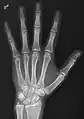

- Hand - DP and Oblique

Left hand by dorsoplantar projection

Lateral projection

Oblique projection